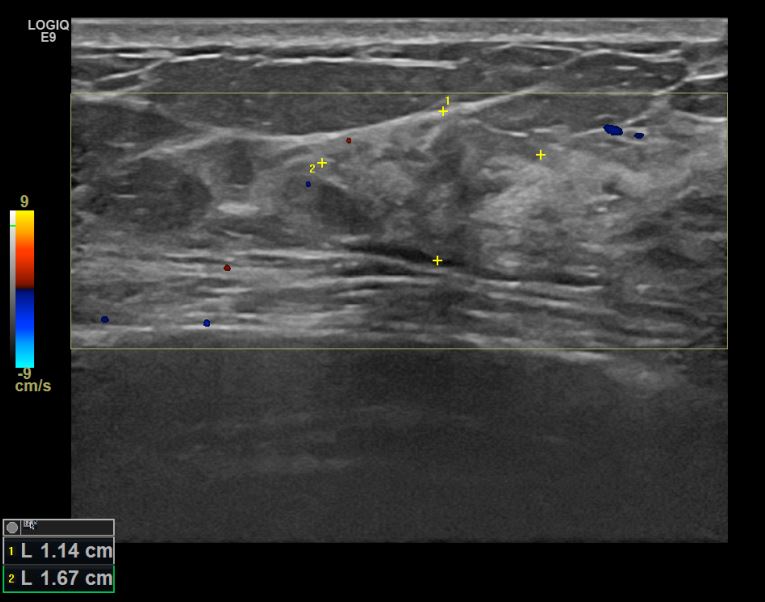

아산유외과개원후 716번째 유방암진단

상기환자 건진상 이상소견으로 조직검사권유받고 내원하신 50대 여성분으로 좌측유방멍울 맘모톰 조직검사시행후 유방암 진단되었습니다.